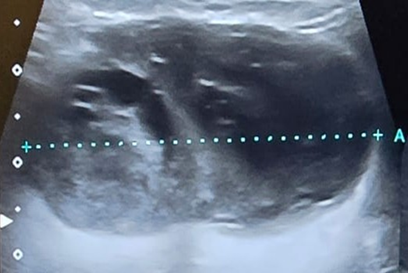

Figure 1: Thyroid ultrasound showed

the presence of a rounded lesion with irregular and poorly defined contours,

rounded morphology, heterogeneous echogenicity, with internal hyperechogenic

areas that could correspond to microcalcifications. The cystic component of the

lesion is observed in the dark sector